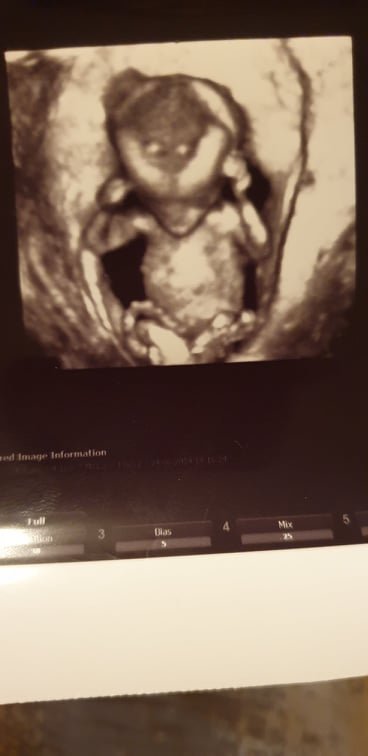

пускам снимка и аз на моето 😁 вече си се фукам с него